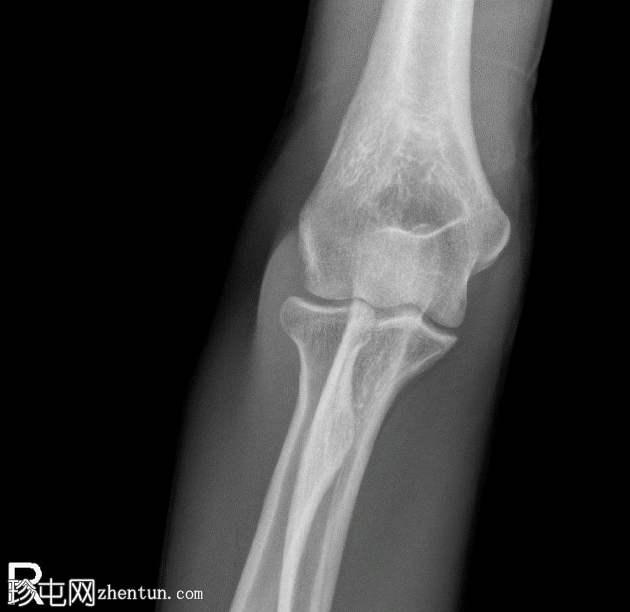

正位片

4.png

桡骨头关节内粉碎性骨折,关节面轻微凹陷。肱骨远端前侧可见移位的骨碎片,桡骨头位片上清晰可见。可见前后脂肪垫征,提示肘关节积液。

未见肘关节脱位,肱桡骨小头排列保持正常。冠突水平可见复合阴影,可能与软组织重叠或投影伪影有关。桡骨和尺骨骨干外观完整,无骨折征。周围软组织肿胀。